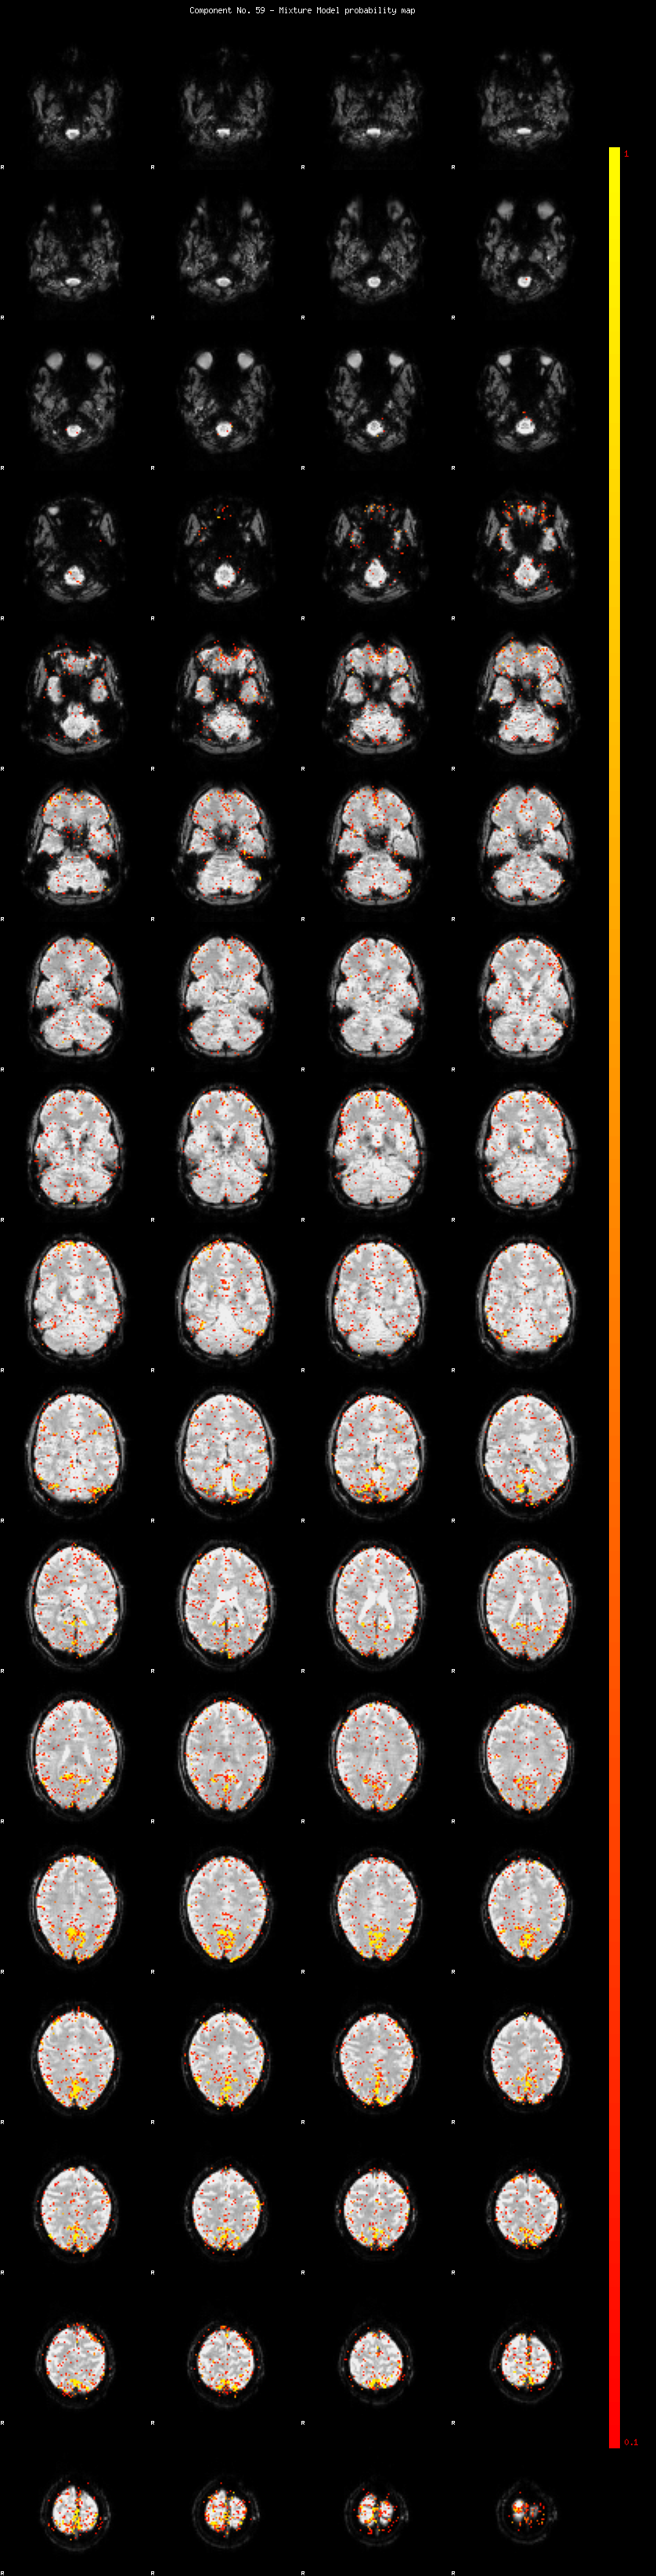

IC_59 Mixture Model fit

Means : 0.000000 2.808469 -2.919104

Vars : 1.000000 3.216771 0.901683

Prop. : 0.961846 0.028769 0.009385